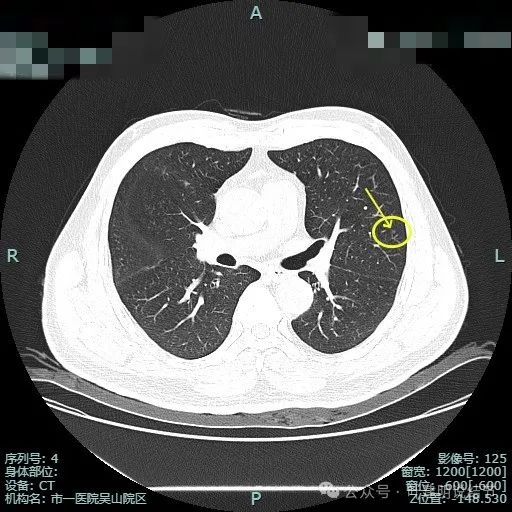

血管异常增粗进入,灶内小空泡征,表面不平有浅分叶,灶内密度感觉欠均匀。

血管进入,边缘细毛刺,灶内小空泡,少许实性成分,表面不平毛糙。

似有月牙铲征,显得像混合密度。

边缘区域表面不平。

左上叶微小磨玻璃结节病灶D,有微小血管进入,但密度太低,风险极小。

右中叶微小磨玻璃结节病灶E,轮廓清,密度甚低,风险极小。